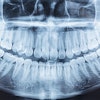

Figure 1: Cropped, reformatted panoramic film of the left mandible.Images courtesy of Dr. Juan F. Yepes.

A 25-year-old man was referred to the oral surgeon by his dentist because of a "lesion" on the left side of his posterior mandible. The patient was asymptomatic. There were no signs of parestheia or swelling.

The patient's past medical history was significant for anxiety and chronic sinus infections. The intraoral and extraoral exams were normal.

The oral surgeon ordered a cone-beam computed tomography (CBCT) scan. Below are the following images:

- A cropped, reformatted pano film of the left mandible

There is a large hypodense lesion (radiolucent), well defined and corticated, extending from the mesial aspect of tooth #17 to the periapical area of tooth #22. The lesion goes from the inferior cortex of the mandible to the alveolar ridge of teeth #18 and #19, the middle third of the root of tooth #20, and the apical third of the root of tooth #21. There is evidence of significant expansion in the coronal and axial projections. No calcifications are observed within the lesion. No periosteal reaction is observed (lingual or buccal). There is no radiographic evidence of perforation of the buccal or lingual walls of the lesion.

There is no radiographic evidence of root resorption or teeth displacement associated with the lesion. No gross caries is present in the teeth involved in the lesion. The inferior alveolar canal is well visualized and displaced buccally-apically by the lesion.